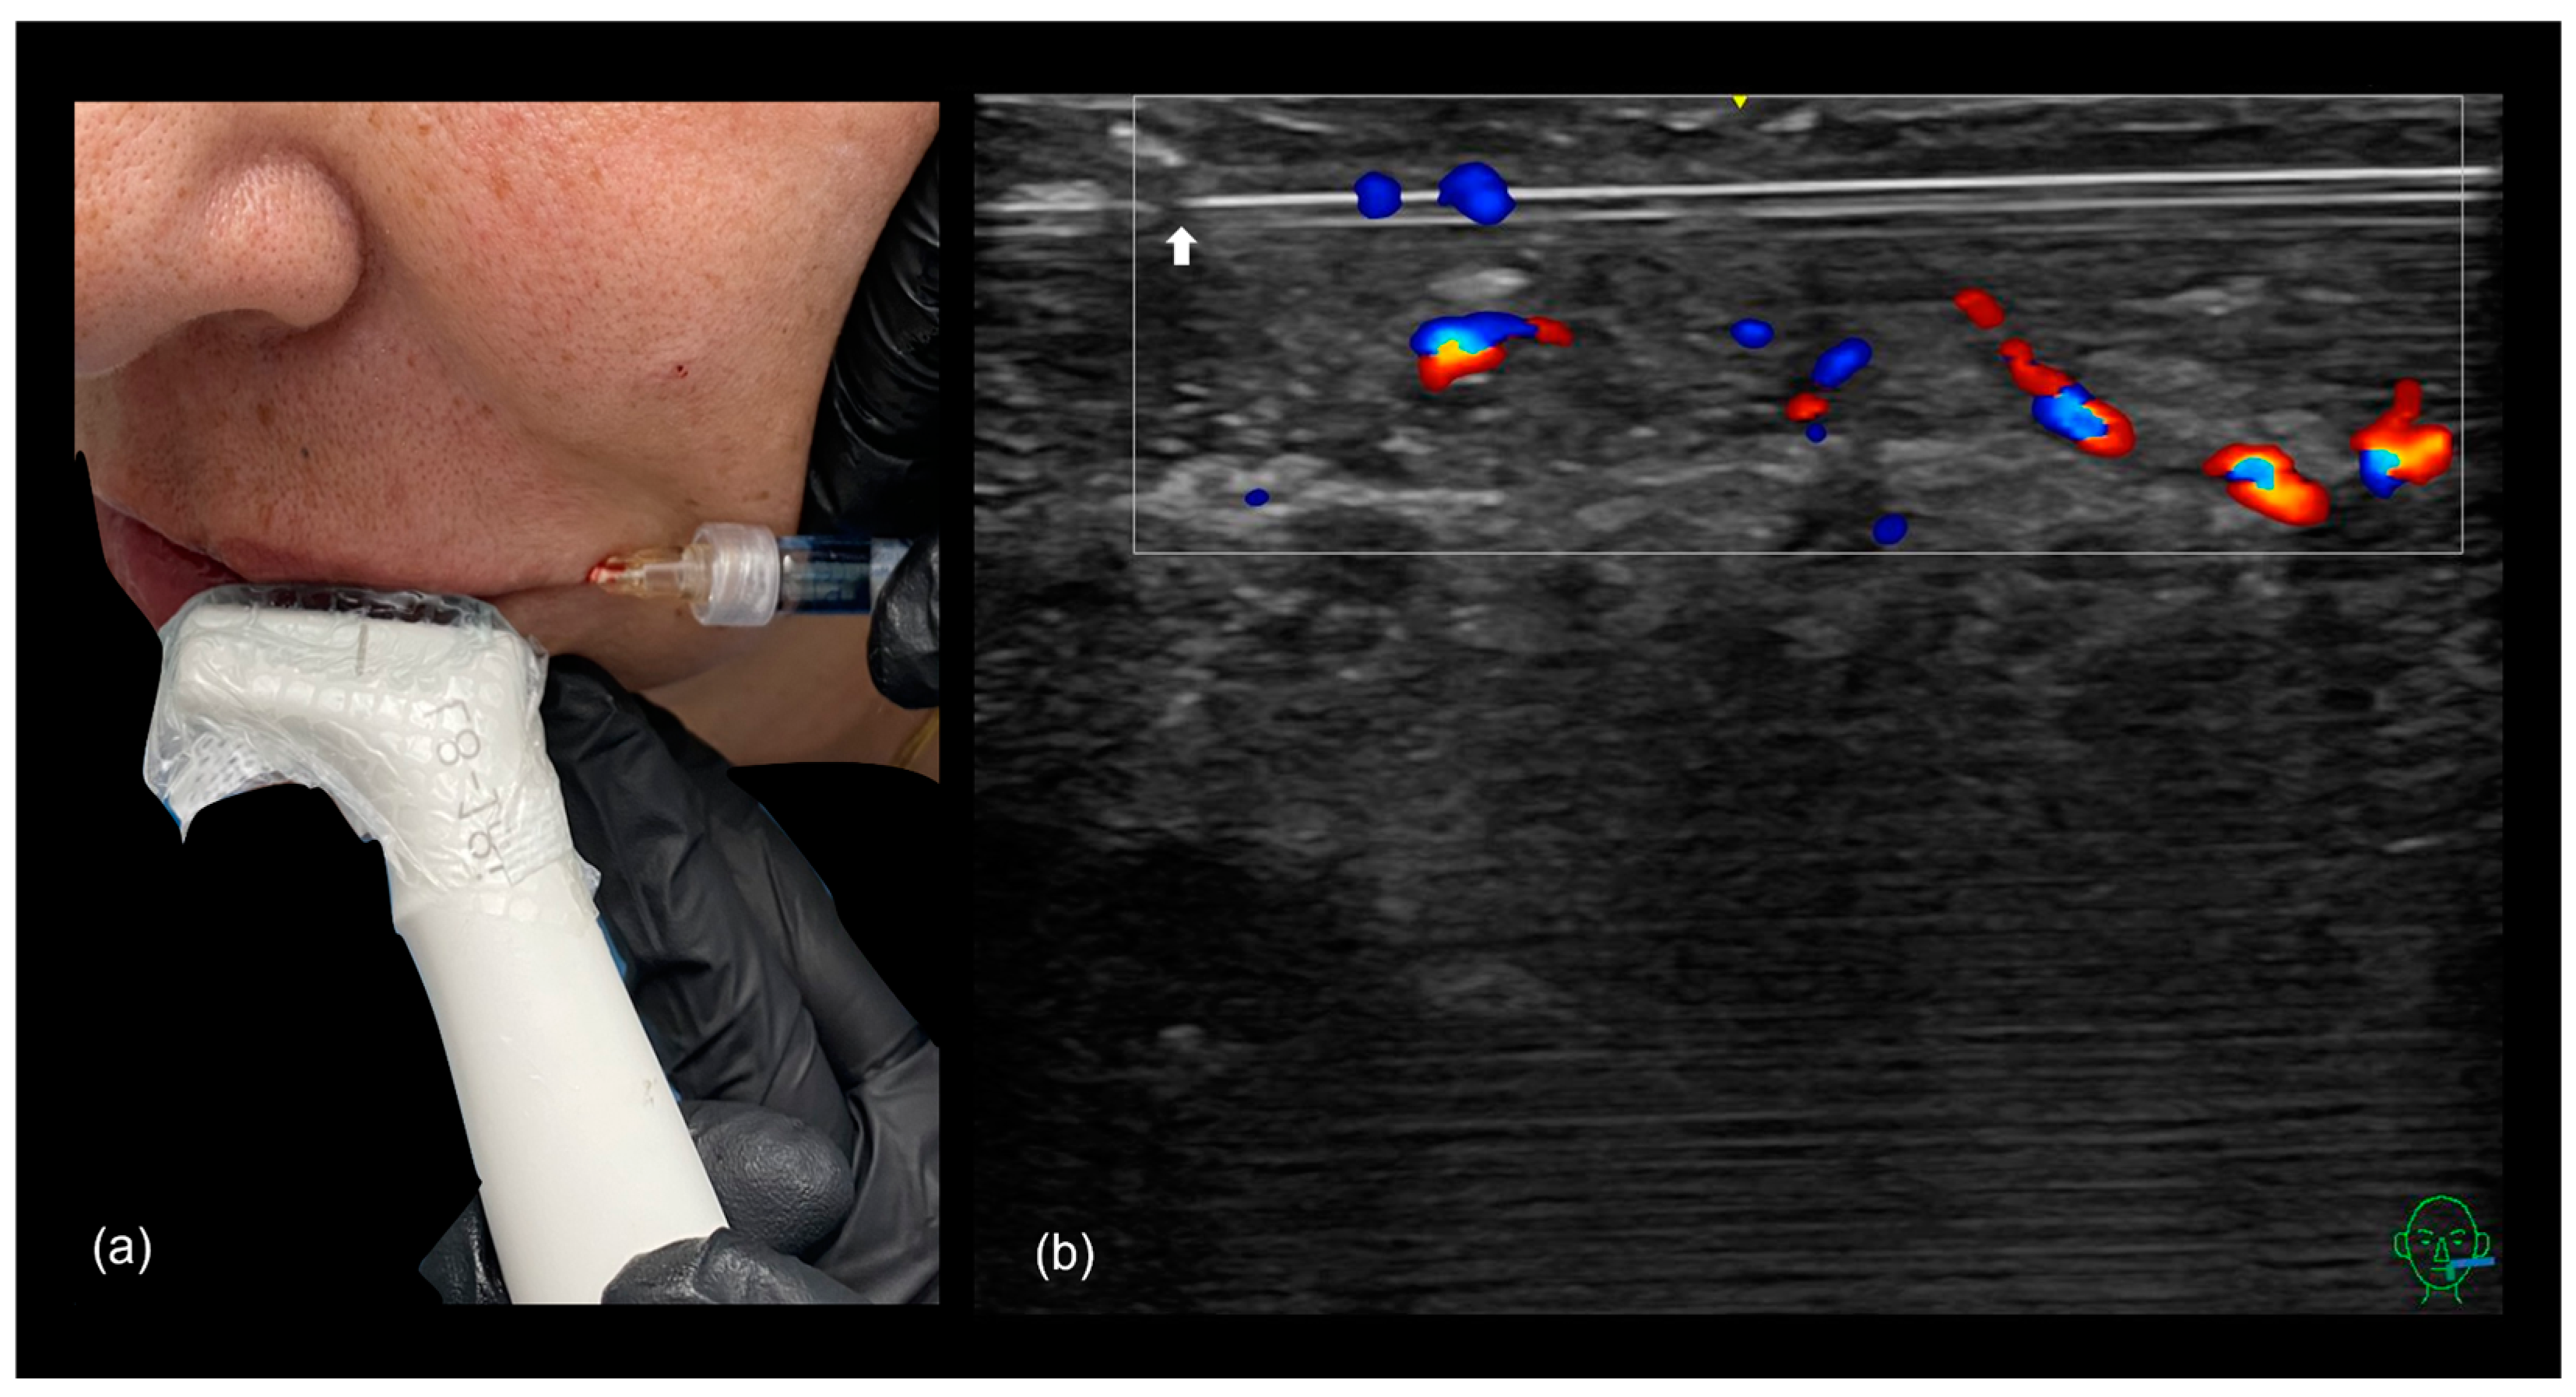

3.3.2. Ultrasound-Guided Filling Techniques of the Lips

- Filling of the Cutaneous Lip

- Filling the vermilion of the lip

- In general, lip filler techniques can be categorized based on the following:

- Injection method: cannula or needle;

- Injection depth: superficial (below the dry mucosa) or deep (submuscular);